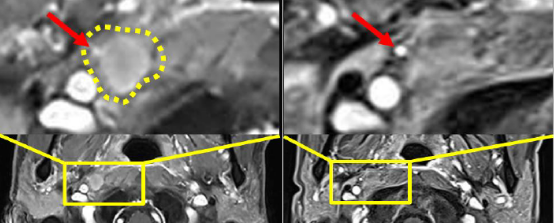

患者在CAR-T回输1周后即反馈右侧眼球疼痛明显缓解,2周后完全无痛感。CAR-T细胞回输后磁共振影像评估显示:患者病灶明显消退,既往被肿瘤压迫的血管重新清晰显影,影像学提示肿瘤组织缩小。经MDT(多学科团队)共同确认,患者病灶达到显著缓解,截至发稿日已随访超245天病情稳定。

左、右分别为患者CAR-T治疗前、后的磁共振检查结果;黄色虚线内为咽后淋巴结区域病灶;红色箭头所指为原先被肿瘤压迫的血管在CAR-T回输后清晰完整显影